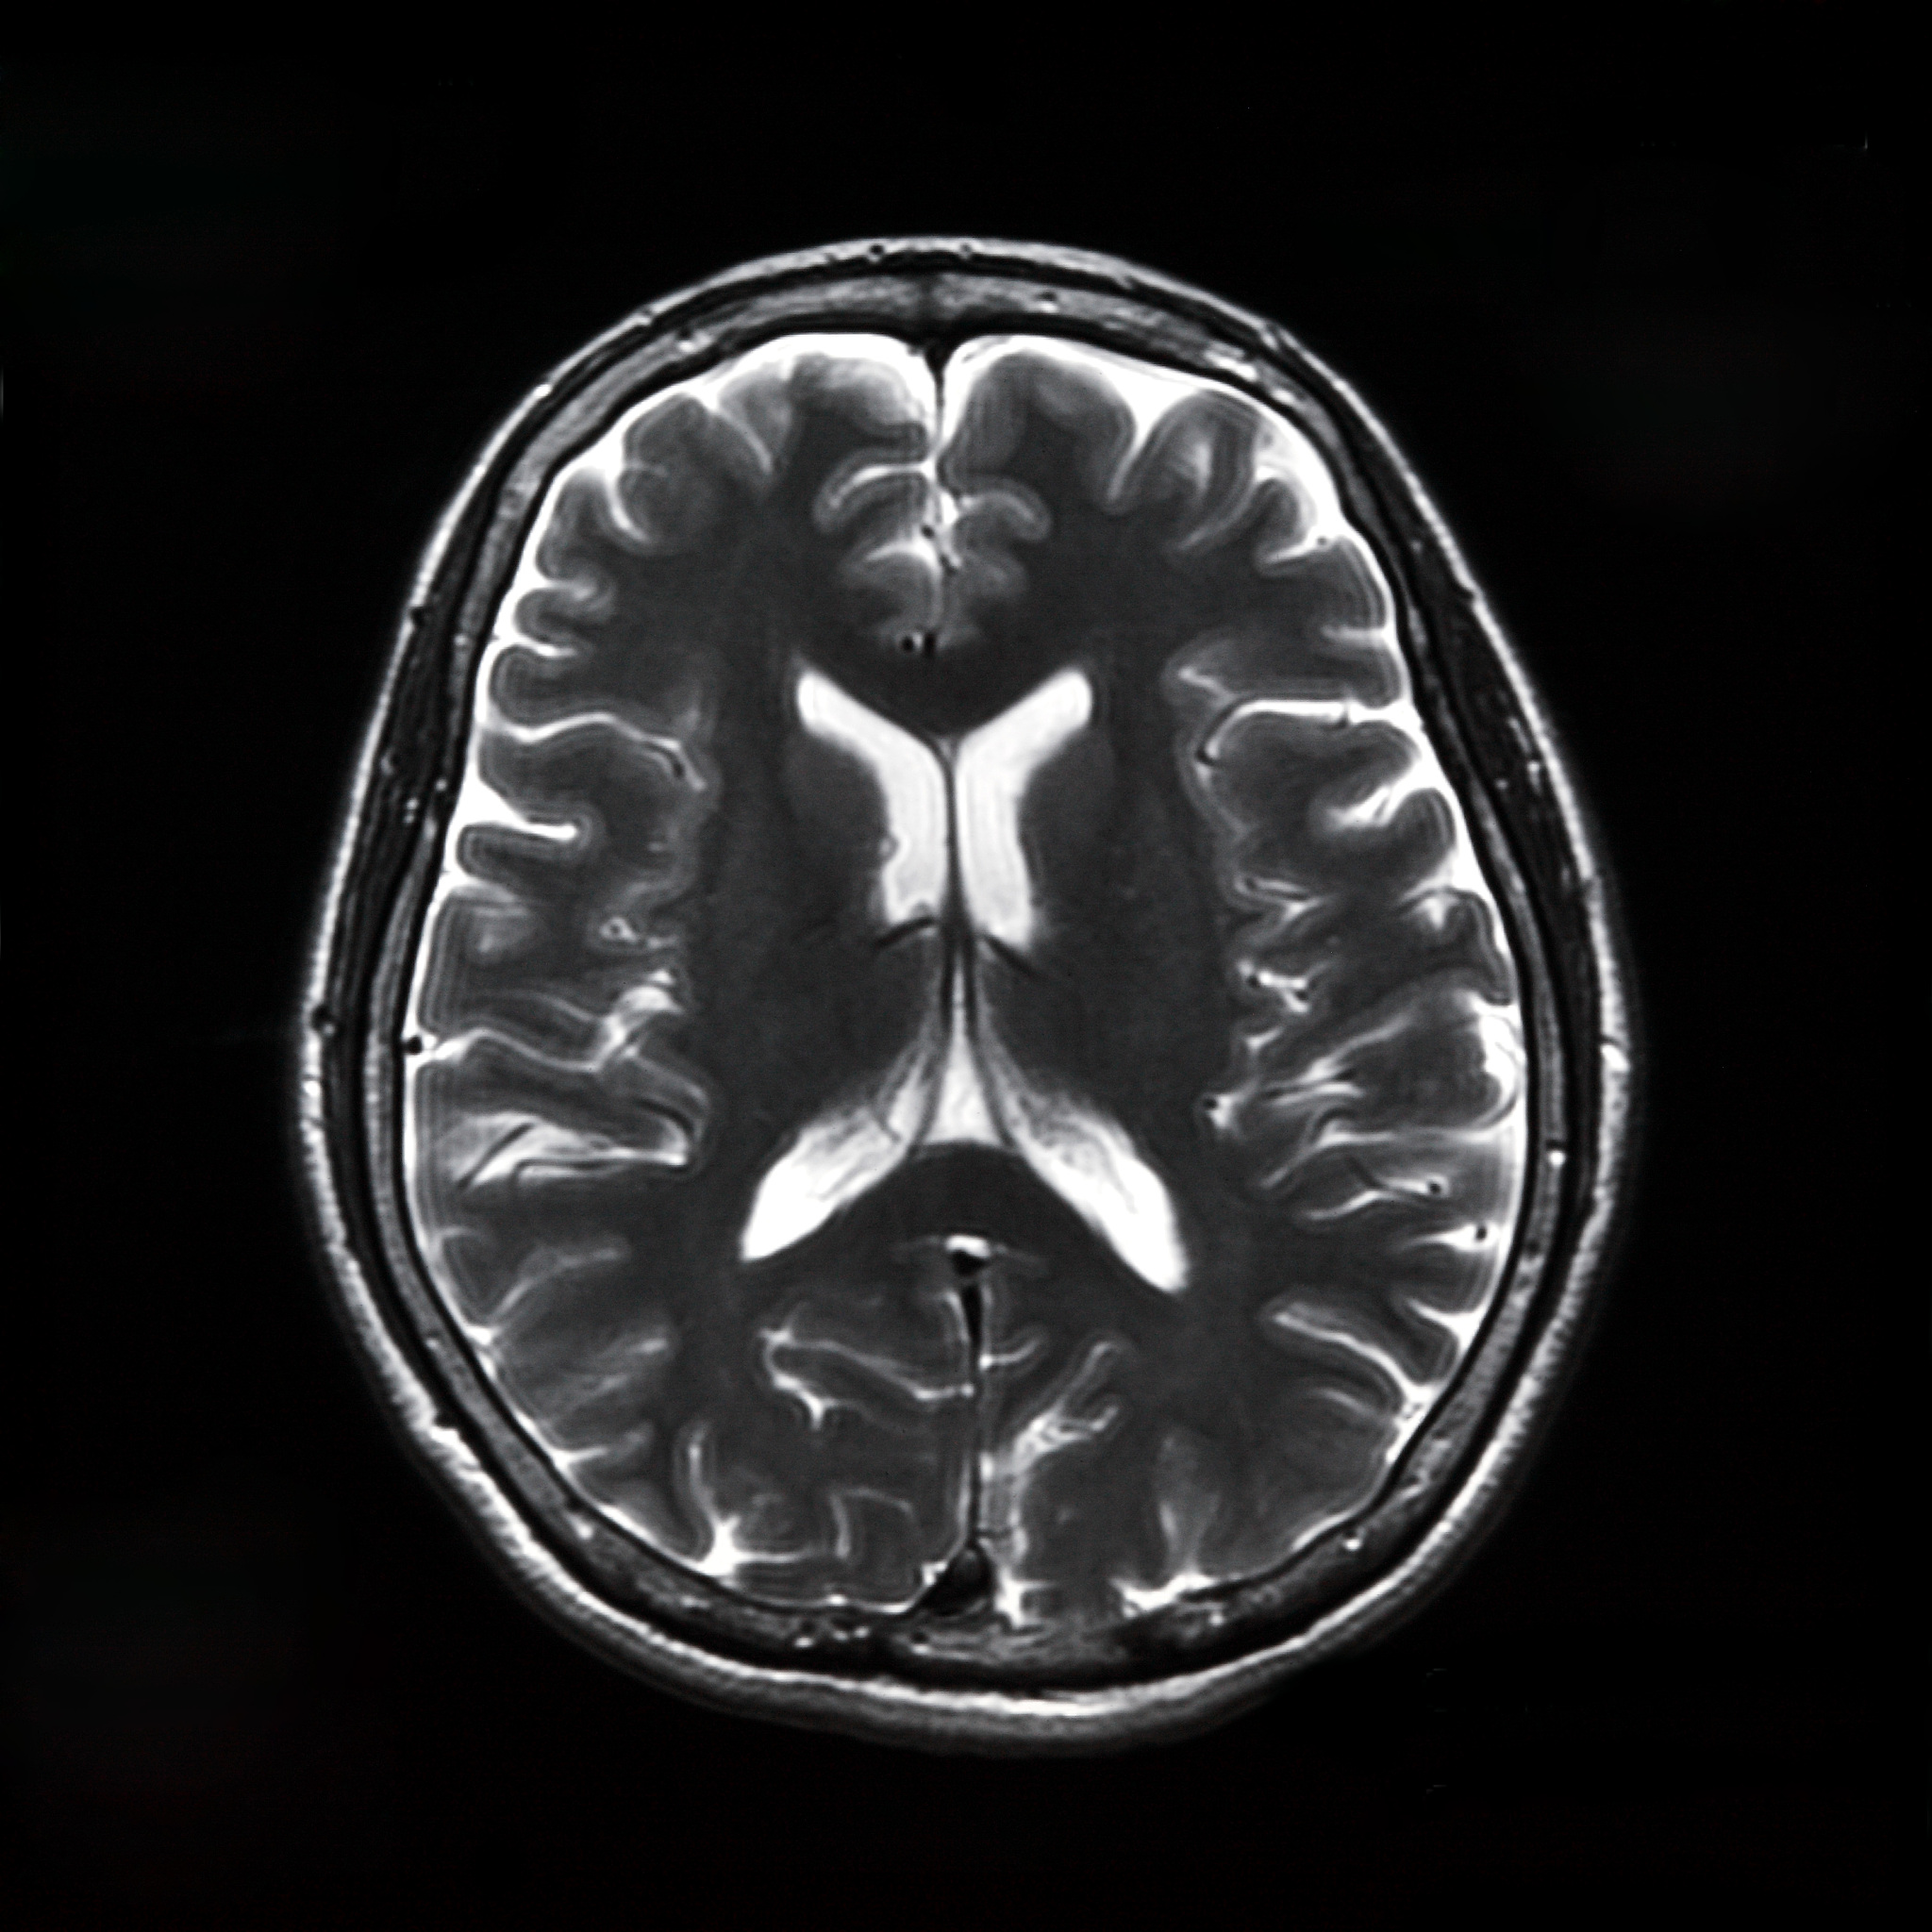

情绪激动可诱发脑梗,尤其在已有动脉硬化基础上,因血压骤升致斑块破裂或血管痉挛,但非根本病因。

1、高血压患者易致小动脉破裂(脑出血)或斑块脱落(脑梗);

2、冠心病者可因应激致心律失常,血栓入脑;

5、但根本原因仍是血管病变。因此,控制基础病比单纯“保持心情”更重要。突发偏瘫即使情绪平稳也需警惕。